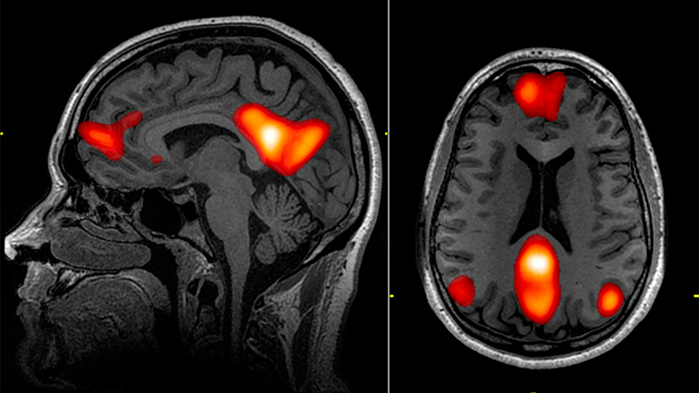

Anderson and his colleagues recruited 168 adult male prisoners to participate in an auditory oddball task, in which participants were instructed to click a button whenever they heard a particular tone. The auditory task was conducted inside a functional magnetic resonance imaging (fMRI) machine that measures activity in various regions of the brain.

The results showed that participants who scored higher on the psychopathy checklist also displayed abnormalities in brain regions associated with attention, including the anterior temporal cortex, medial prefrontal cortex, dorsal anterior cingulate, temporoparietal junction, and posterior cingulate cortex.